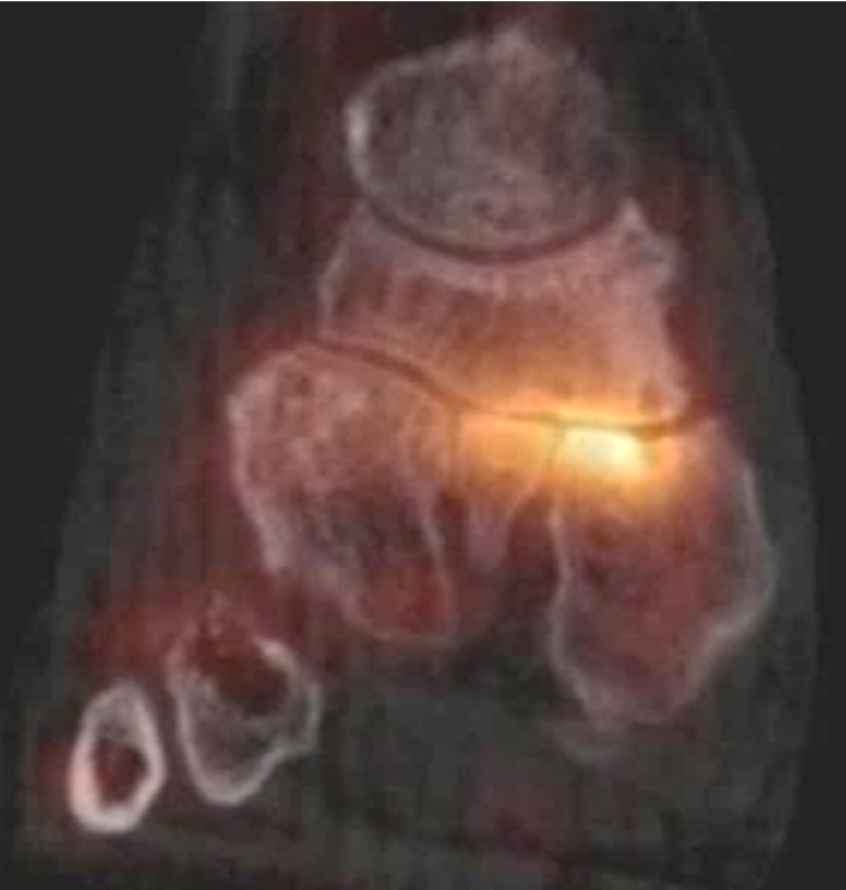

Die Abbildungen 4.2.a bis d zeigen den typischen Aspekt einer talacalcanearen Coalitio. Es besteht nur eine linksseitige, symptomatische Coalitio talocalcaneare (4.2.a und c); das 35 Tage zuvor angefertigte MRT zeigt keine auffälligen Signalveränderungen (4.2.b und d).